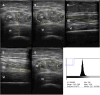

Muscle wasting and low muscle mass are prominent features of protein energy wasting (PEW), sarcopenia and sarcopenic obesity in patients with chronic kidney disease (CKD). In addition, muscle wasting is associated with low muscle strength, impaired muscle function and adverse clinical outcomes such as low quality of life, hospitalizations and increased mortality. While assessment of muscle mass is well justified, the assessment of skeletal muscle should go beyond quantity. Imaging techniques provide the means for non-invasive, comprehensive, in-depth assessment of the quality of the muscle such as the infiltration of ectopic fat. These techniques include computed tomography (CT), magnetic resonance imaging (MRI) and ultrasound. Dual energy X-ray absorptiometry is also an imaging technique, but one that only provides quantitative and not qualitative data on muscle. The main advantage of imaging techniques compared with other methods such as bioelectrical impedance analysis and anthropometry is that they offer higher precision and accuracy. On the other hand, the higher cost for acquiring and maintaining the imaging equipment, especially CT and MRI, makes these less-used options and available mostly for research purposes. In the field of CKD and end-stage kidney disease (ESKD), imaging techniques are gaining attention for evaluating muscle quantity and more recently muscle fat infiltration. This review describes the potential of these techniques in CKD and ESKD settings for muscle assessment beyond that of muscle quantity.